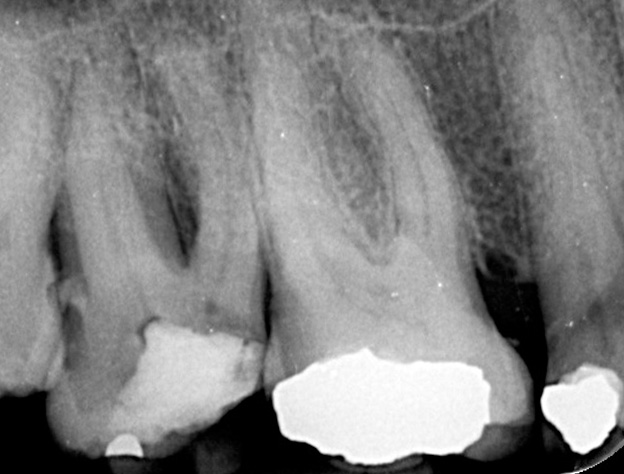

Gallery - Root Canal Treatment

Case 3

Before After